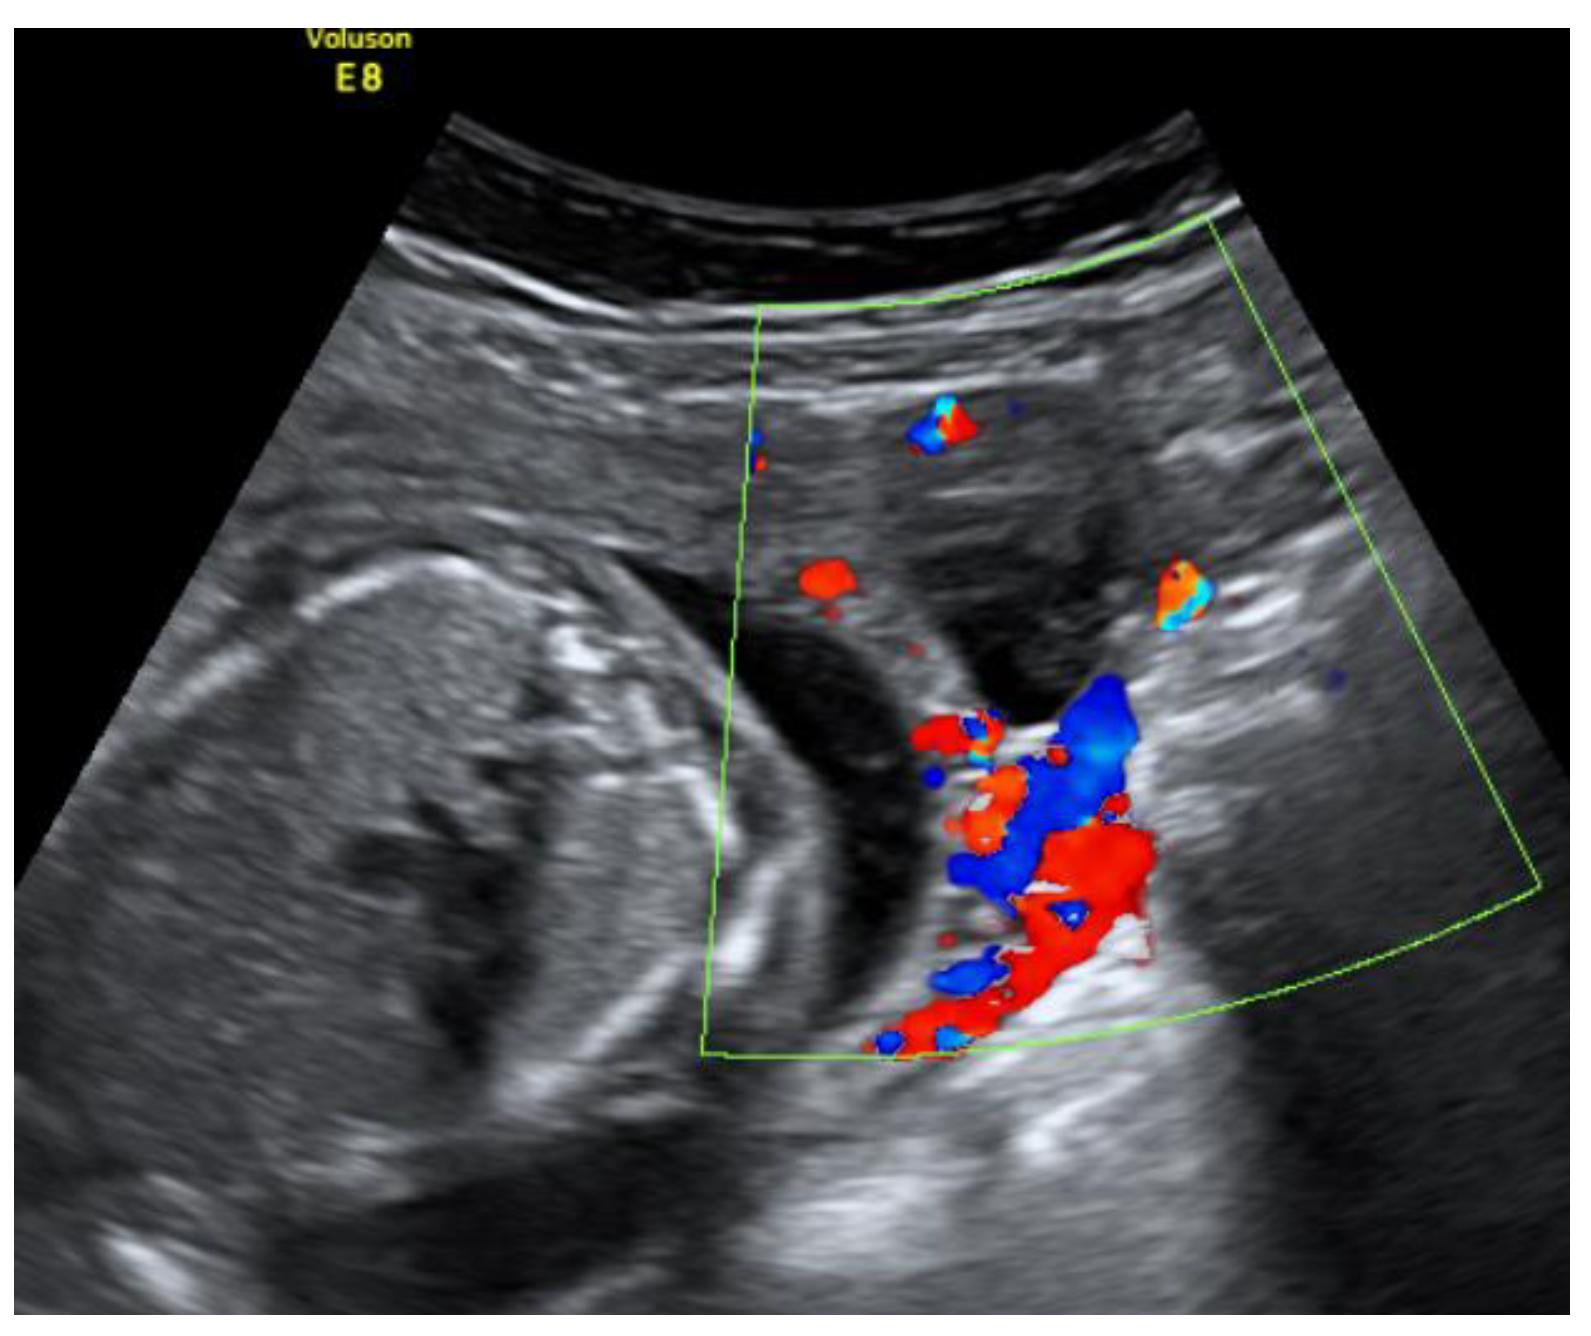

On the 22nd week of gestation, the woman was admitted to tertial level hospital complaining of pain in hypogastric and left iliac regions of the abdomen, provoked by physical exercise. Ultrasonography was performed, the remaining unchanged mass in the left cornu of the uterus was observed as well as an intraamniotic septum in the lower segment of the uterus, as shown in Figure 5 and Figure 6. The fetal growth of the intrauterine pregnancy was unaffected and matched its gestational age. Conservative treatment was chosen, the pain resolved and the patient was discharged in 2 days.

Figure 5. Left cornu of the uterus visualized by transabdominal ultrasonography at the 22nd week of gestation.